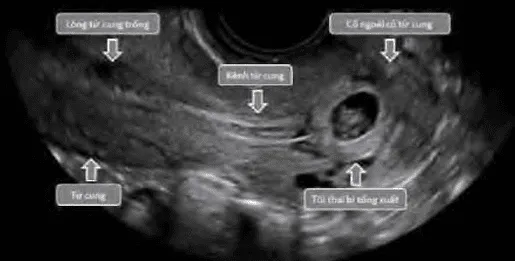

- Trứng trống (blighted ovum): Chỉ sự hiện diện của túi thai nhưng không thấy phôi thai bên trong.

- Thai ngưng phát triển sớm: Chỉ hình ảnh túi thai có phôi nhưng không có hoạt động tim thai.

Phần tiêu đề “Sảy thai khó tránh”Ra máu kèm mở cổ tử cung khi thai vẫn còn trong buồng tử cung. Cần phân biệt với thai ngoài tử cung ở cổ tử cung bằng β-hCG và siêu âm.